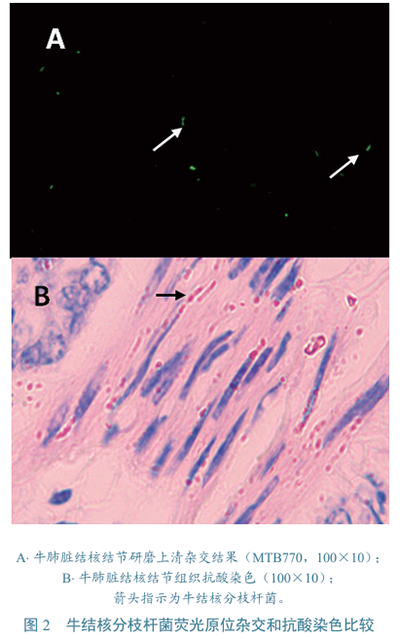

牛結核分歧桿菌???牛結核分枝桿菌樣品雜交前,須用二甲苯和溶菌酶處理(也可使用消色肽酶,但非必須),二者缺一不可。二甲苯需處理至少20 min,溶菌酶需消化30 min,以充分去除表面的酸類物質,從而獲得充分的通透性,便于探針進入并與RNA雜交。45 ℃雜交4 h,可獲得最佳效果,縮短雜交時間會影響信號強度。因此,牛結核分枝桿菌的檢測時間較長,需6~8 h。從牛肺臟結核結節研磨液上清中,成功檢測到牛分枝桿菌(圖2-A),經抗酸染色檢出較多的抗酸菌(圖2-B)。結核病陽性牛鼻腔拭子中,未檢出典型的牛結核分枝桿菌。